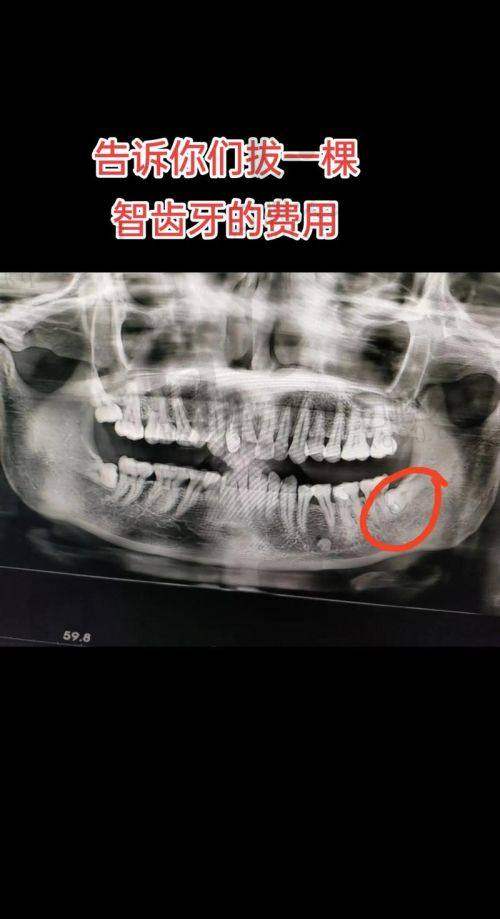

智齿问题一直困扰着特别多人,不少人都有过被智齿折磨的经历。在深圳,如果你正为下颌正位萌出智齿的拔除而烦恼,那么深圳友睦口腔推出的拔下颌正位萌出智齿499元起这个项目可不要错过。接下来就为大家详细介绍一下这个项目的相关情况。

深圳友睦口腔此次推出的拔下颌正位萌出智齿项目价格为499元起。在深圳地区,一般下颌正位智齿拔除价格在800-2500元之间,相比之下,深圳友睦口腔的这个价格是特别有优势的。不过需要注意的是,每个人的口腔情况不同,具体的费用可能会有所差异,这里的价格仅供参考哦。

除了下颌正位萌出智齿,深圳友睦口腔对于其他类型智齿的拔除也有相应的价格。上颌正位智齿拔除难度较小,价格相对亲民,大型牙科医院价格在500-1000元,友睦口腔的收费也会在合理范围内;而埋伏阻生智齿,由于完全埋在牙龈或骨头里,拔除难度大,费用一般在1500-3000元起。